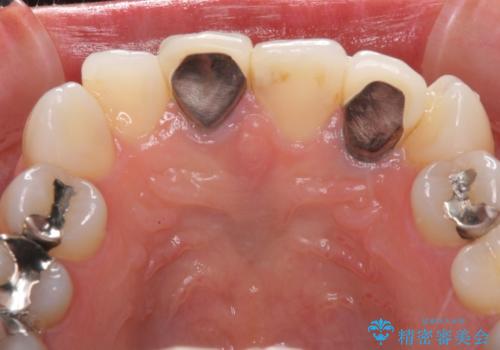

- 20年ほど前に被せた前歯のメタルボンドクラウンの色合いを気にして来院された患者様です。

裏打ちが金属の場合、どうしても金属色を遮蔽しないとならないため、透明感のない色合いとなってしまいます。